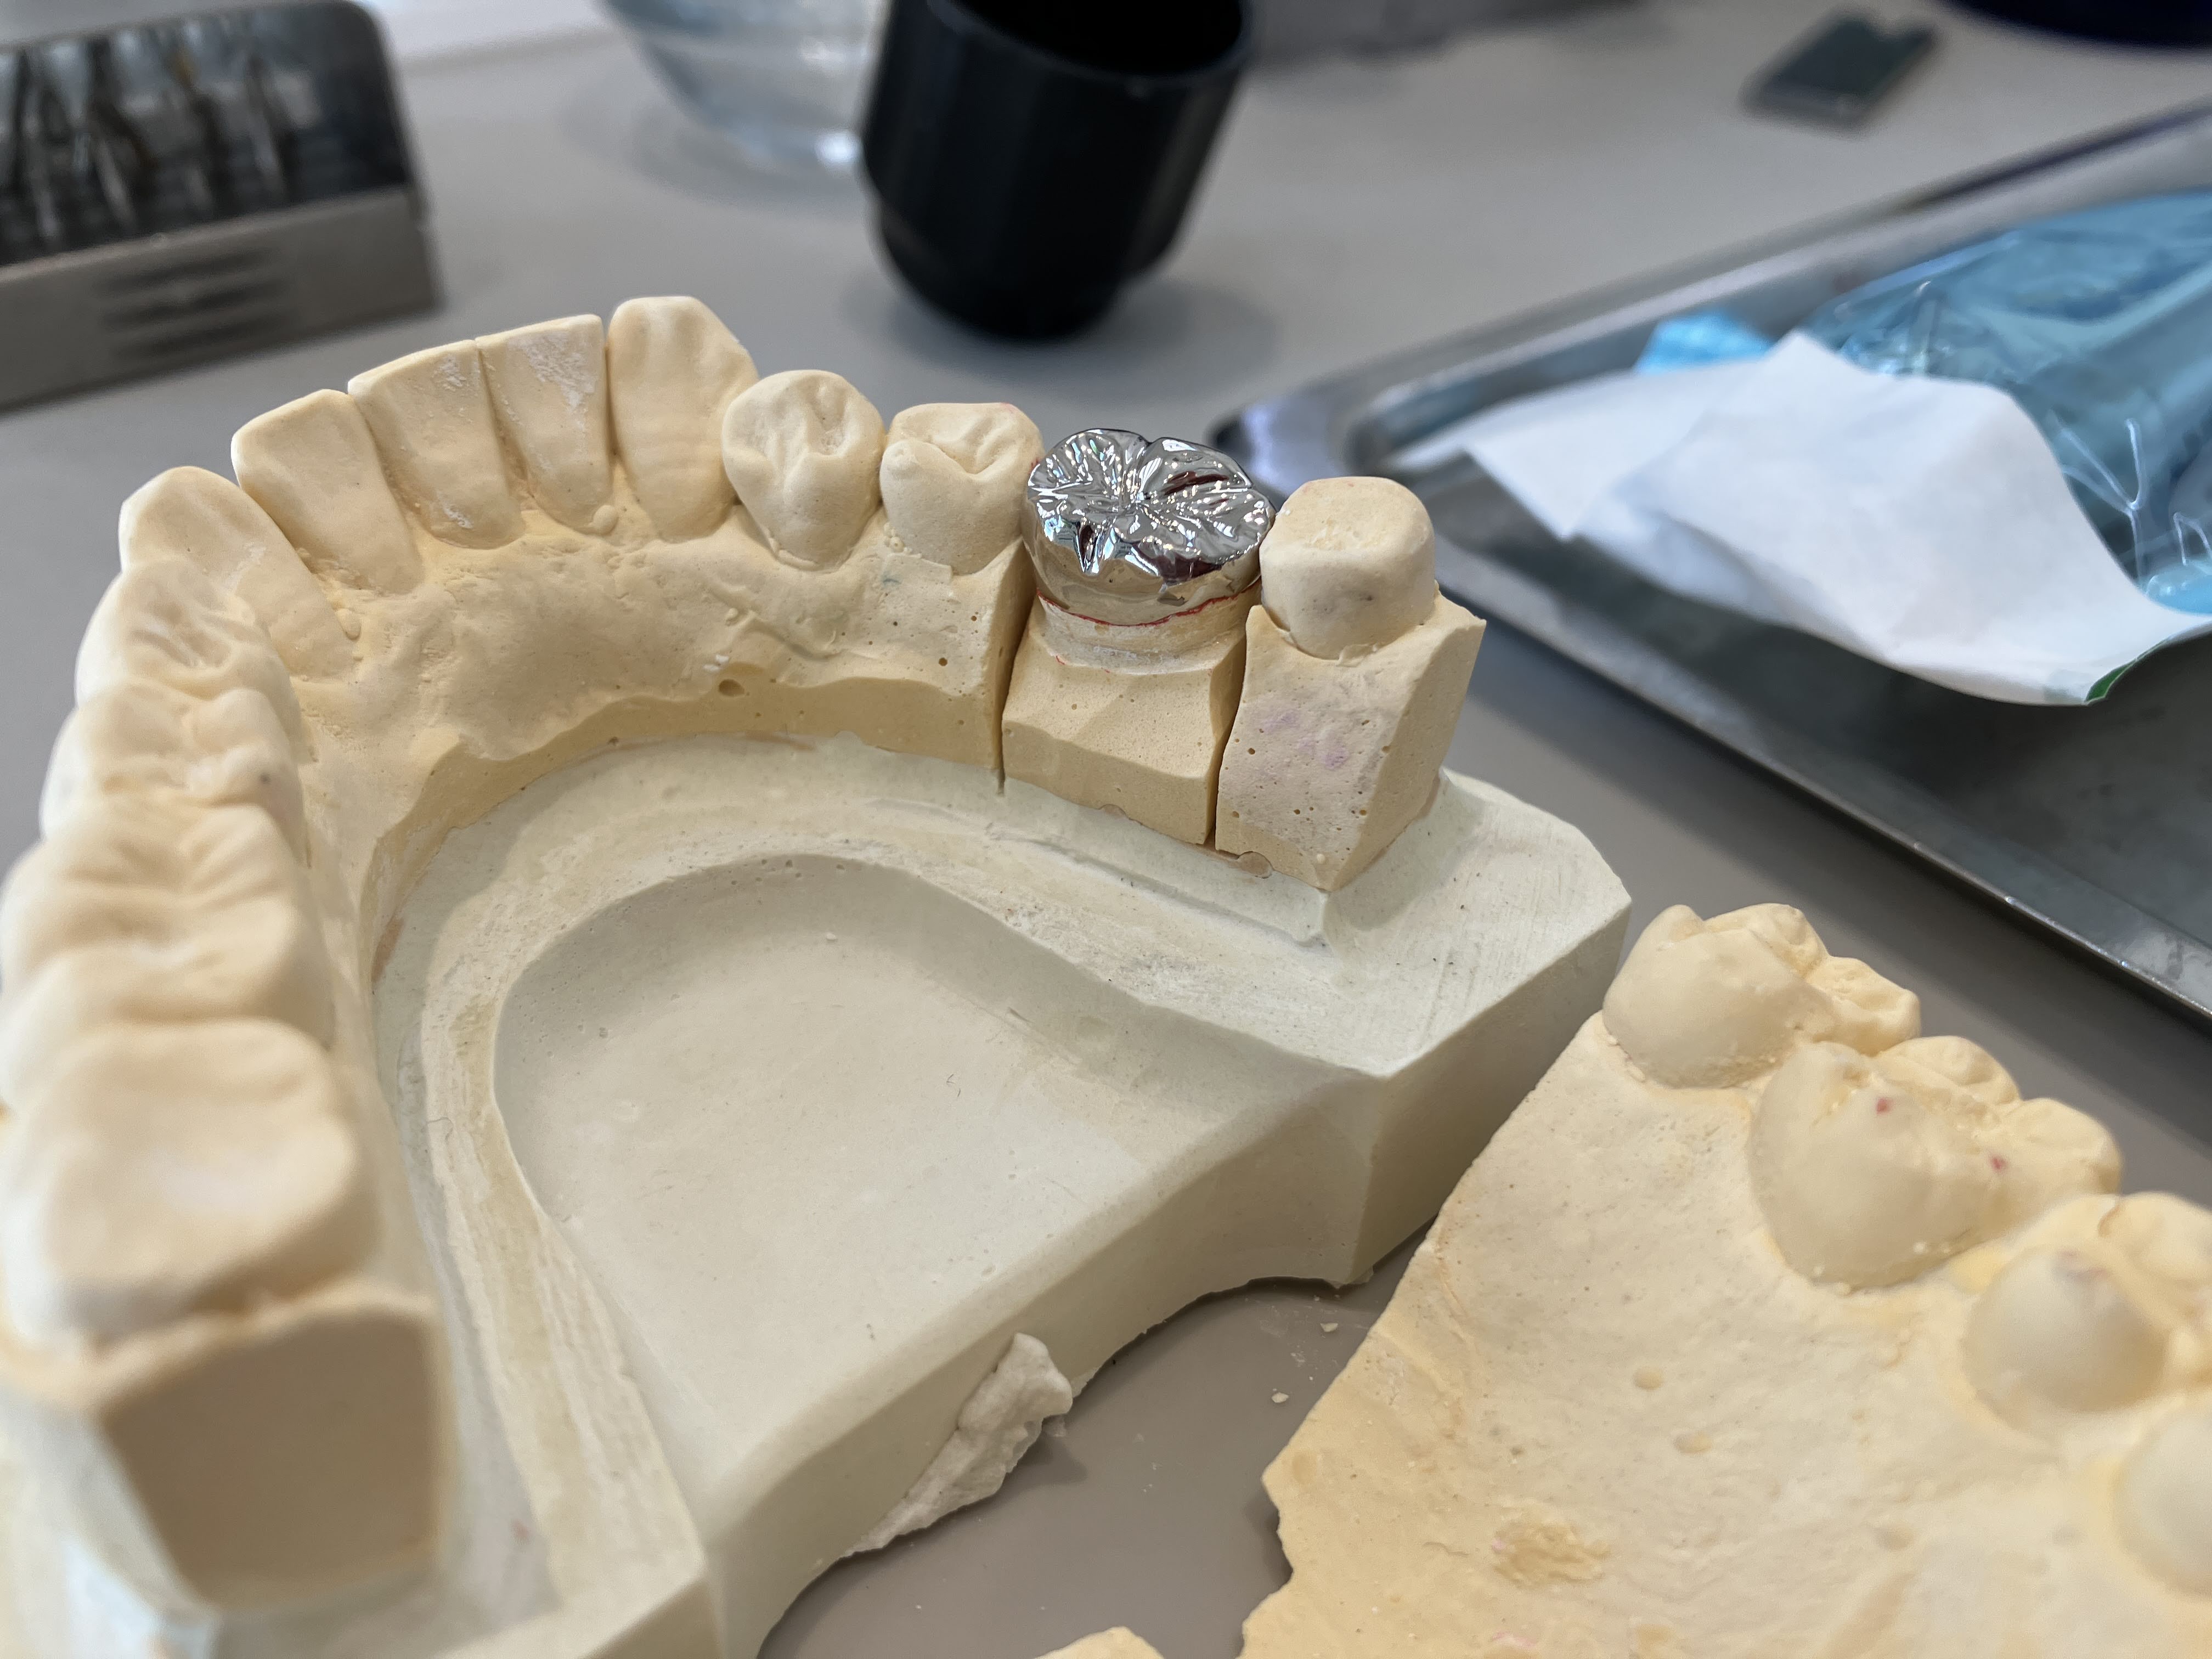

2024年6月7日(金) 銀冠